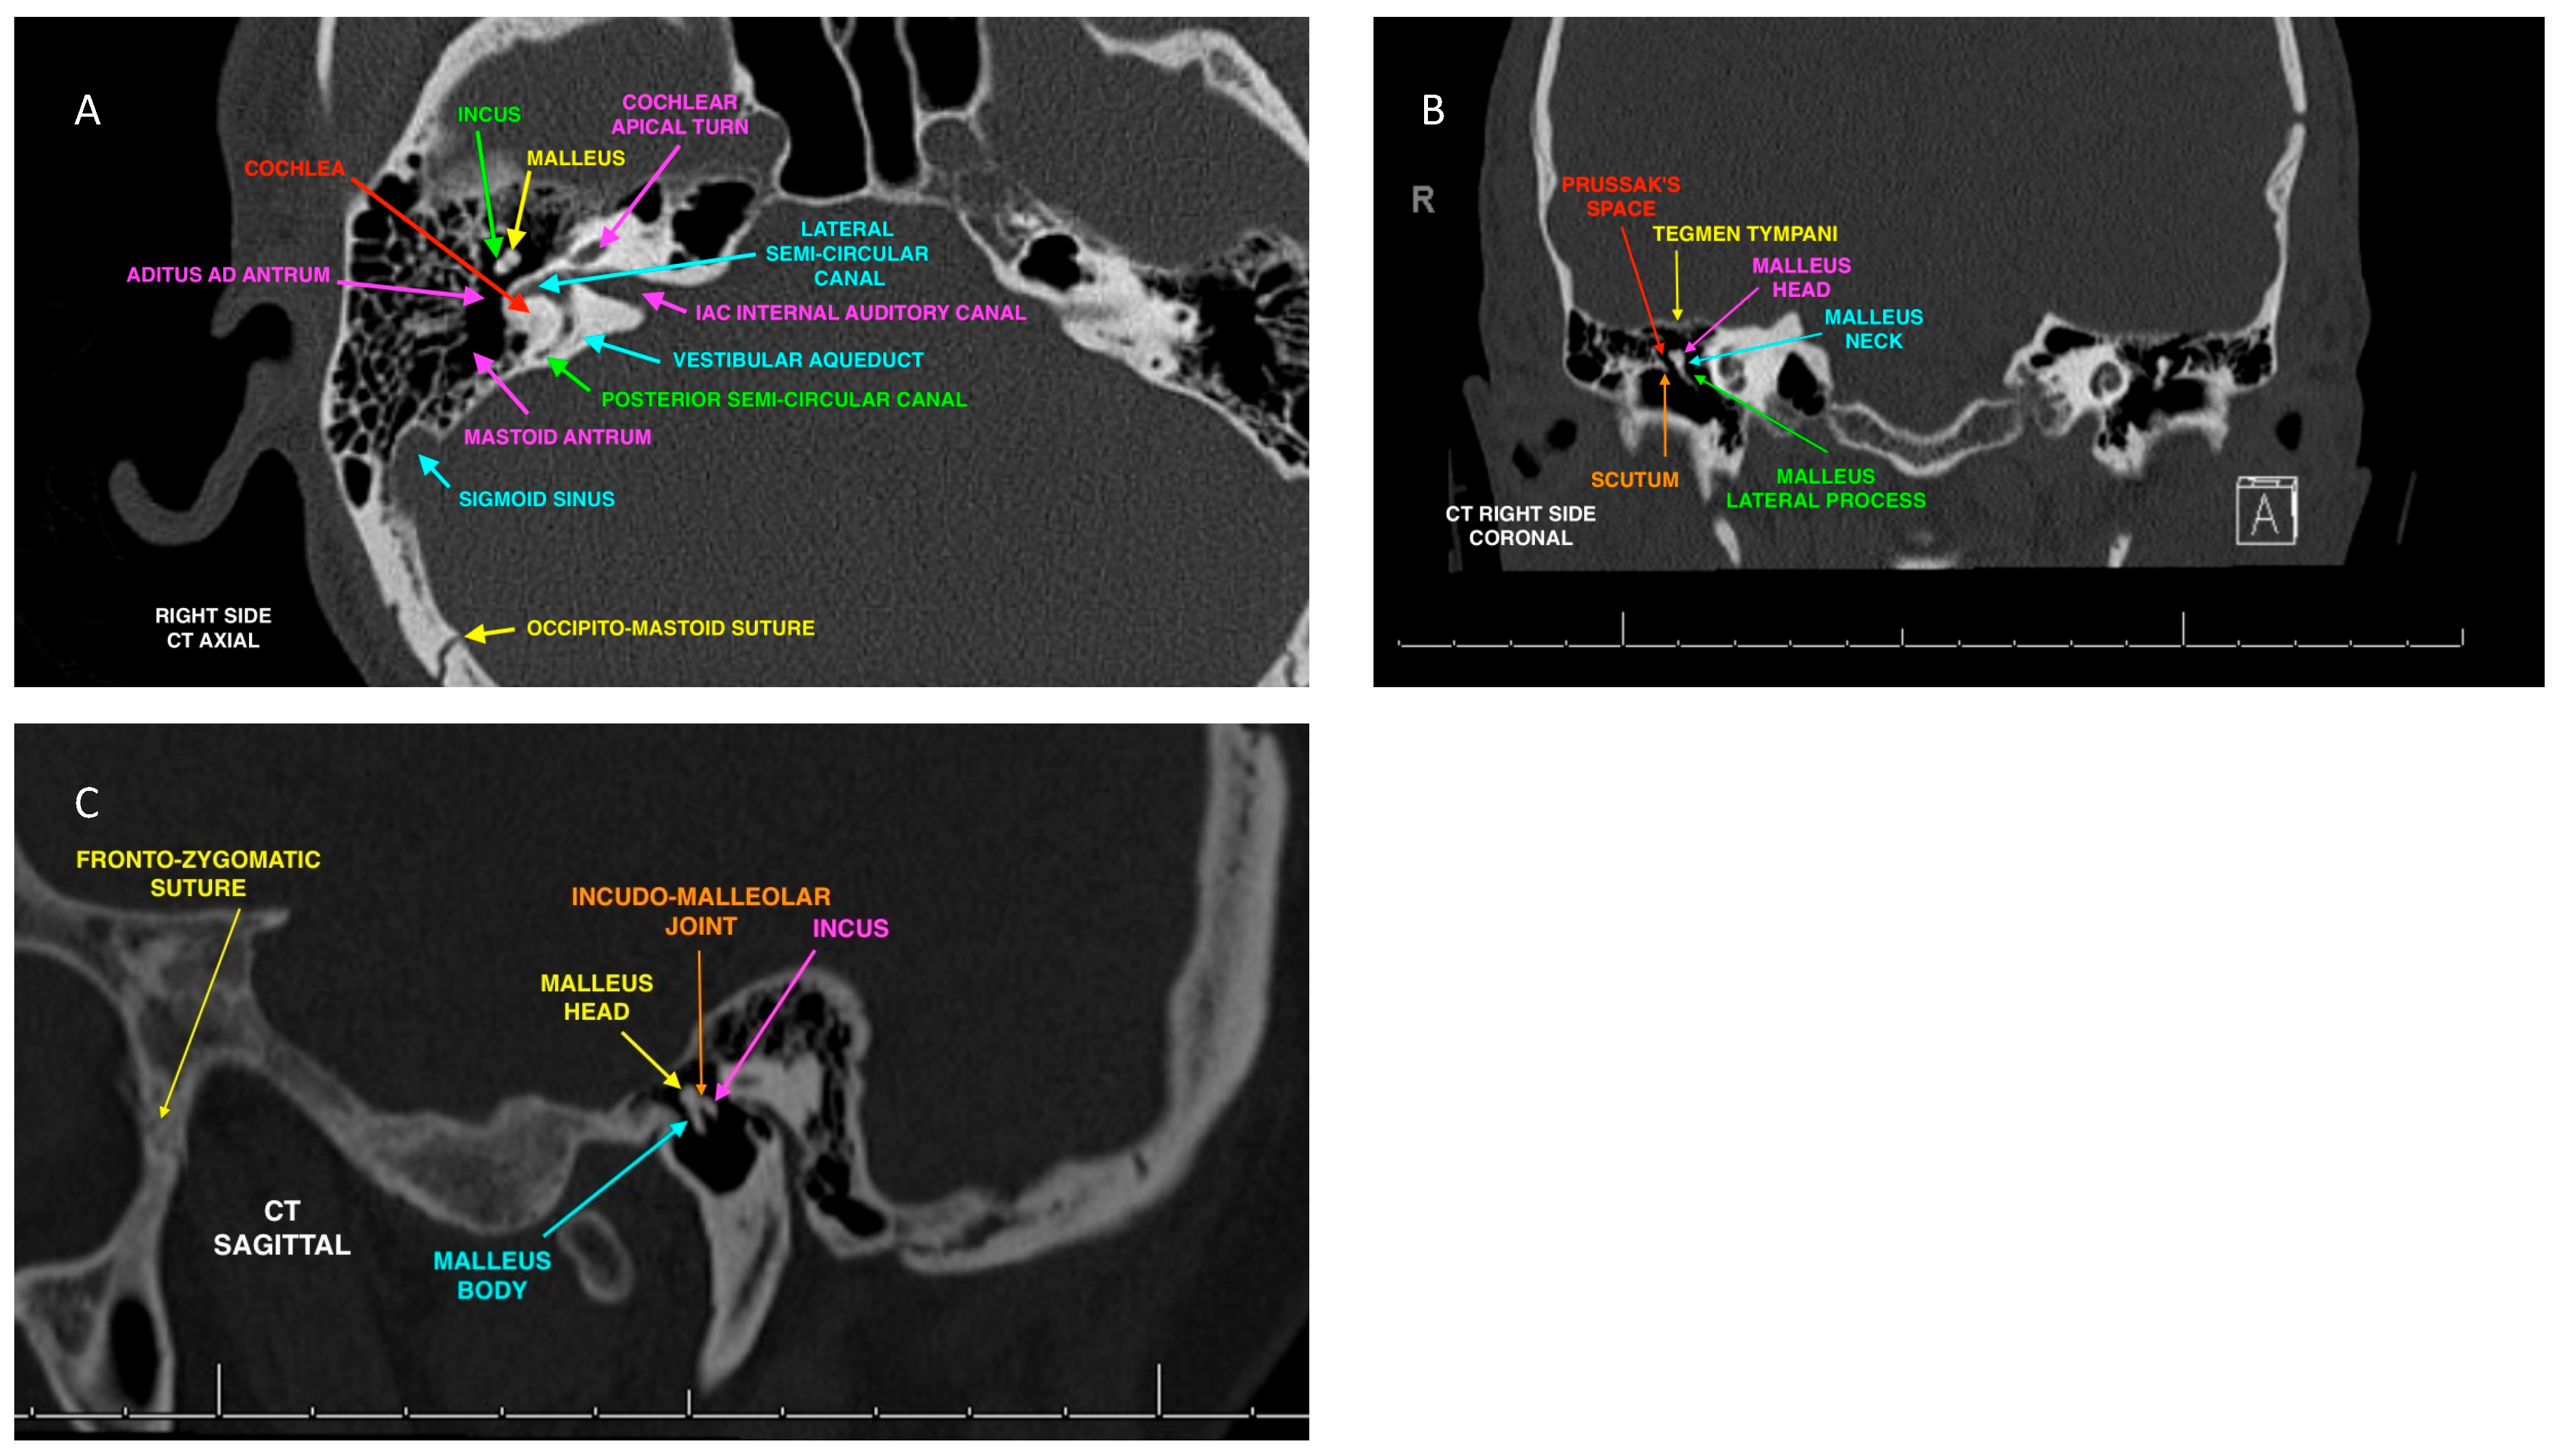

| Hospital patient | Normal anatomy of the ossicular chain | CT Scan | Present, complete |